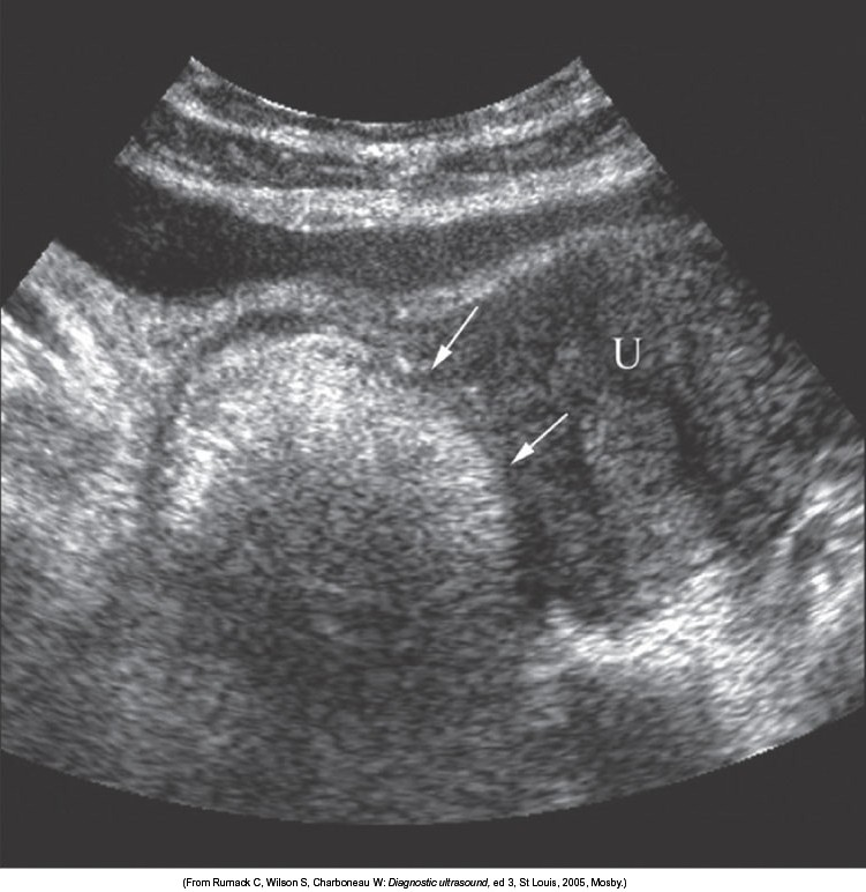

Bicornate Uterus

*